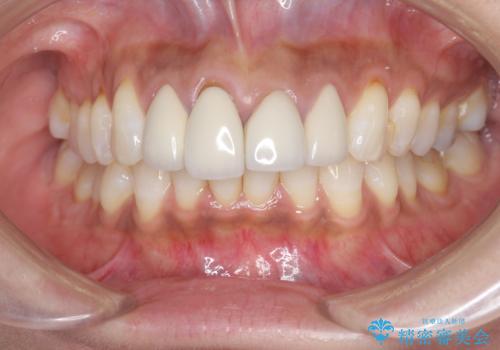

金属色の見える前歯 オールセラミックで審美治療

- 前歯のクラウンの見た目が不自然、歯の根元が見えたり金属色が気になるので改善したい、とセラミック治療を希望され来院されました。

歯肉の位置変化による審美障害を改善するため、オールセラミックジルコニアクラウンで再治療を行い審美性の改善を計画します。

見た目が自然になり、色調も天然の歯とおなじような透明感のある色調が再現され、大変喜んでいただくことができました。